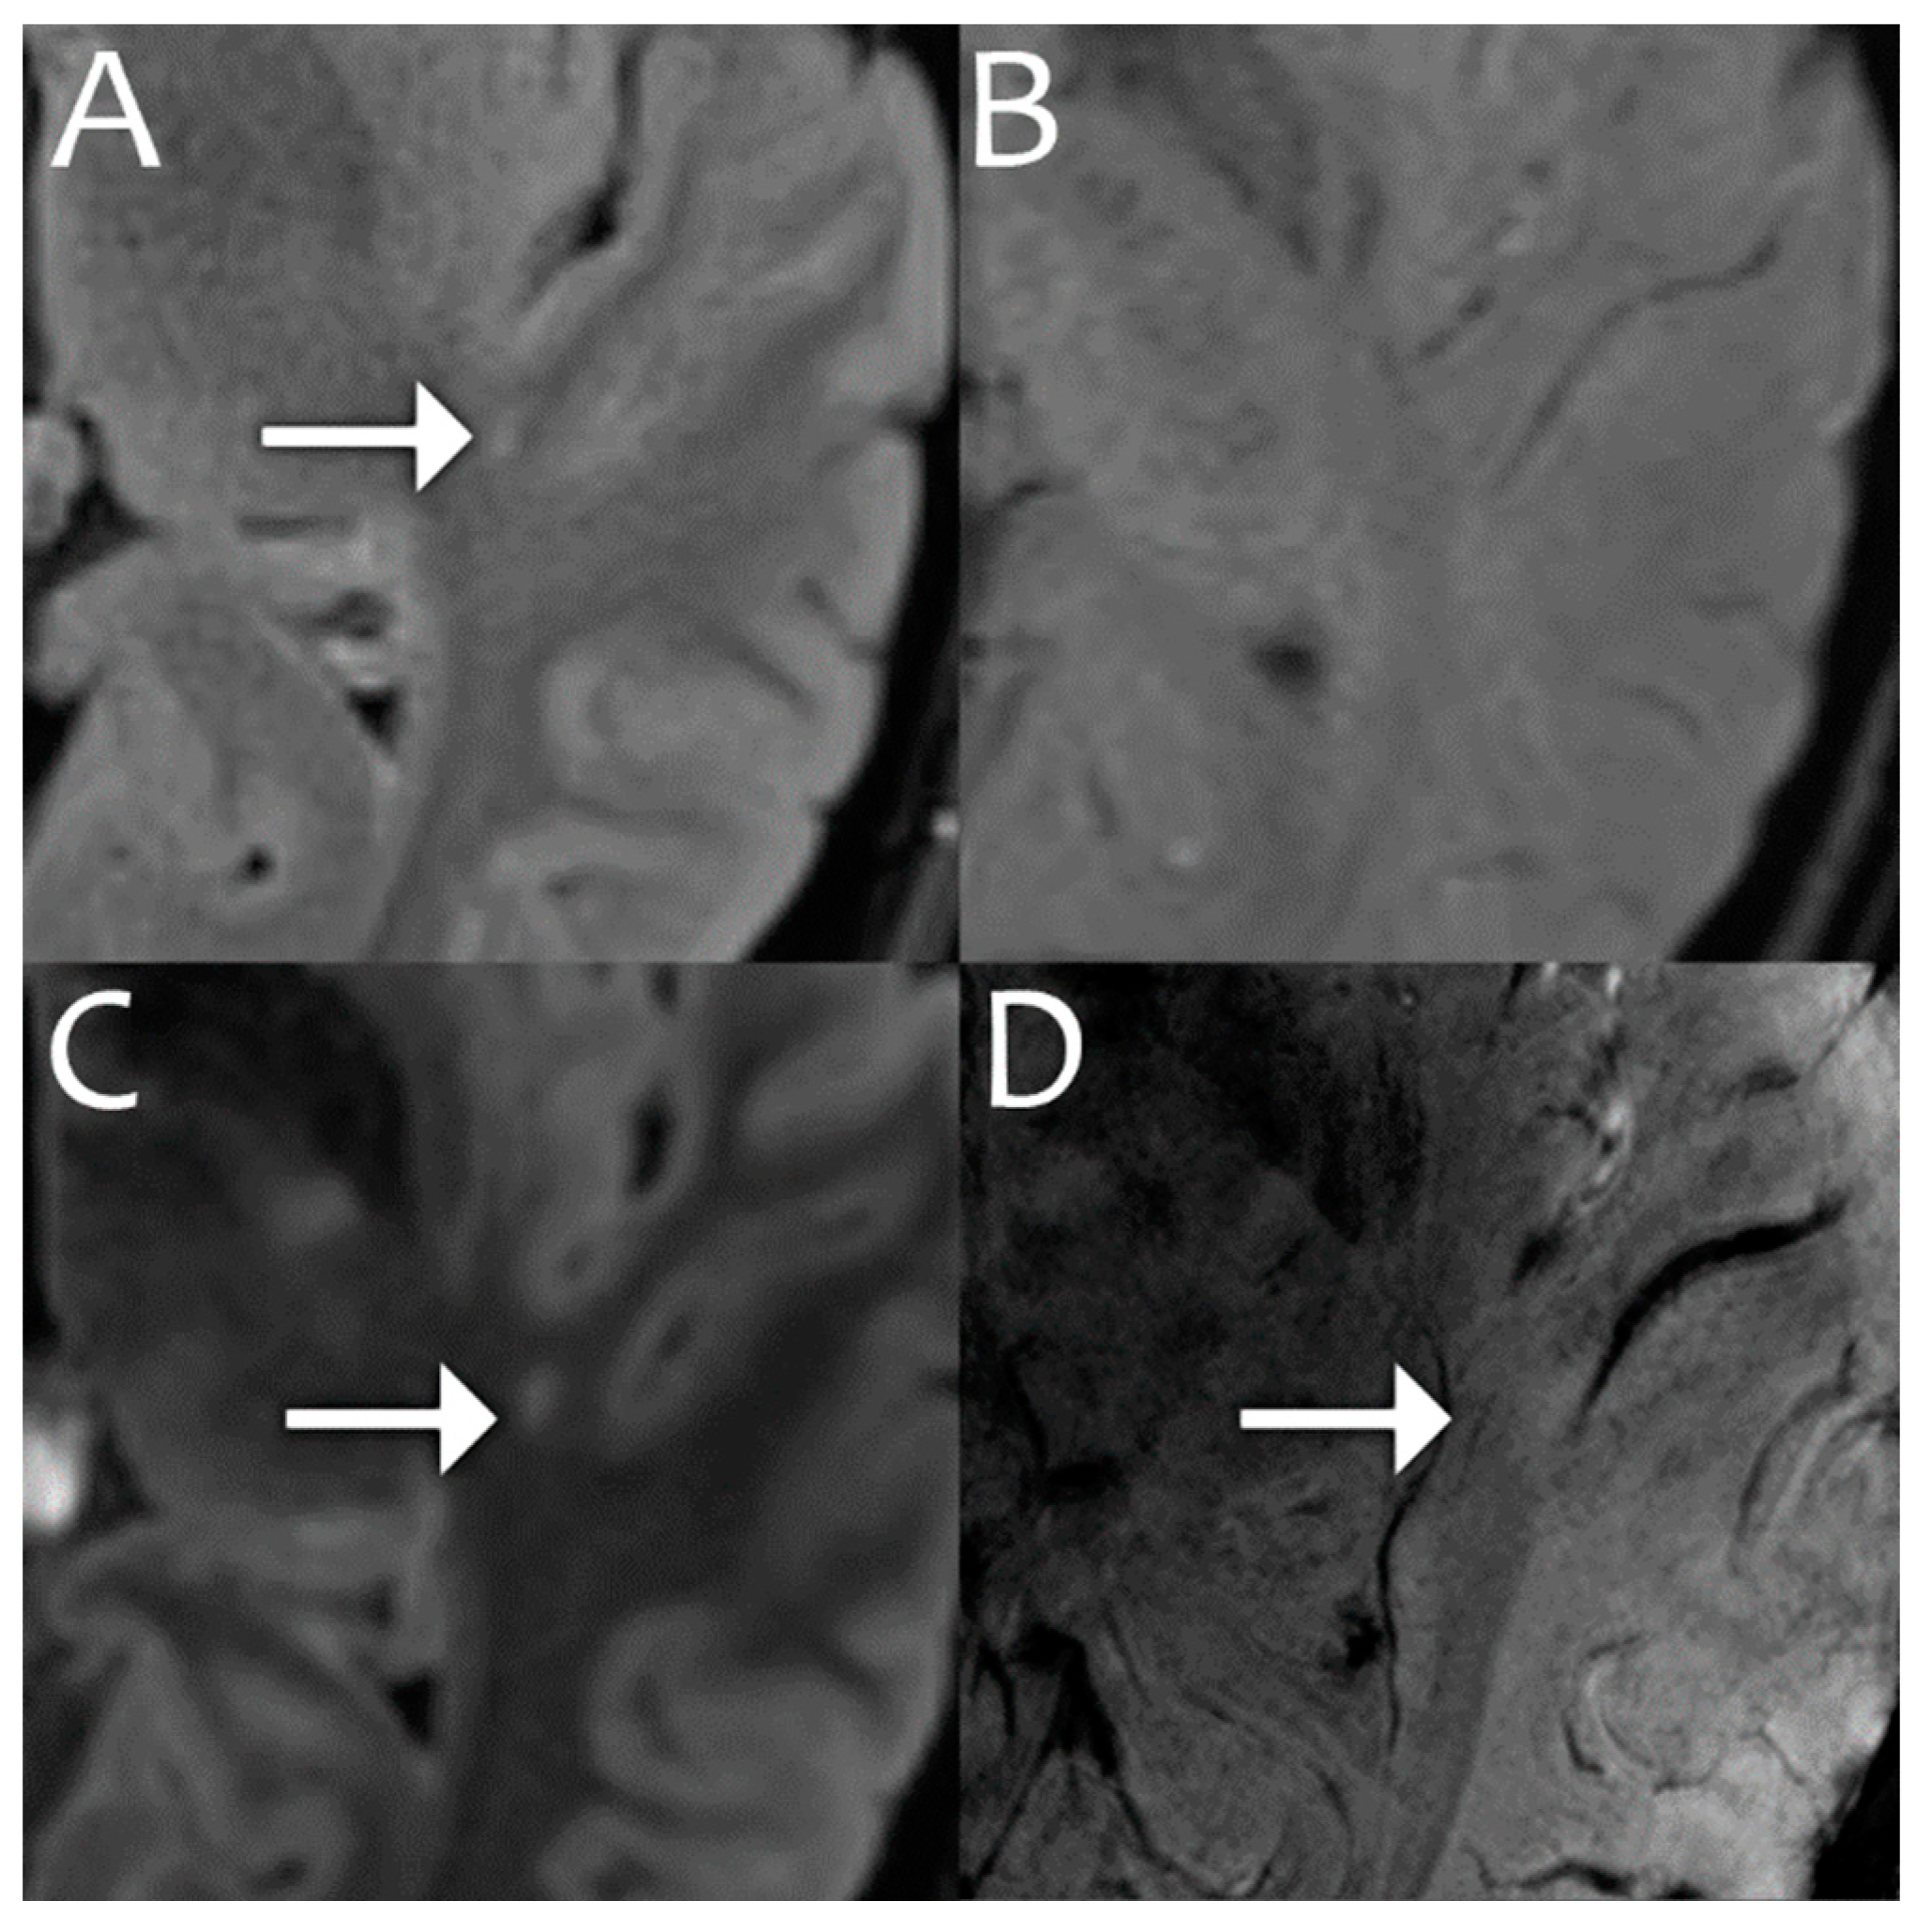

- Veersema, T.J.; Ferrier, C.H.; van Eijsden, P.; Gosselaar, P.H.; Aronica, E.; Visser, F.; Zwanenburg, J.M.; de Kort, G.A.P.; Hendrikse, J.; Luijten, P.R.; et al. Seven tesla MRI improves detection of focal cortical dysplasia in patients with refractory focal epilepsy. Epilepsia Open 2017, 2, 162–171. [Google Scholar] [CrossRef]

- Okromelidze, L.; Patel, V.; Singh, R.B.; Chiriboga, A.S.L.; Tao, S.; Zhou, X.; Straub, S.; Westerhold, E.M.; Gupta, V.; Agarwal, A.K.; et al. Central Vein Sign in Multiple Sclerosis: A Comparison Study of the Diagnostic Performance of 3T versus 7T MRI. Am. J. Neuroradiol. 2023, 45, 76–81. [Google Scholar] [CrossRef]

- Clarke, M.A.; Cheek, R.; Kazimuddin, H.F.; Hernandez, B.; Clarke, R.; McKnight, C.D.; Derwenskus, J.; Eaton, J.; Irlmeier, R.; Ye, F.; et al. Paramagnetic rim lesions and the central vein sign: Characterizing multiple sclerosis imaging markers. J. Neuroimaging 2023, 34, 86–94. [Google Scholar] [CrossRef]

- Özütemiz, C.; White, M.; Elvendahl, W.; Eryaman, Y.; Marjańska, M.; Metzger, G.J.; Patriat, R.; Kulesa, J.; Harel, N.; Watanabe, Y.; et al. Use of a Commercial 7-T MRI Scanner for Clinical Brain Imaging: Indications, Protocols, Challenges, and Solutions—A Single-Center Experience. Am. J. Roentgenol. 2023, 221, 788–804. [Google Scholar] [CrossRef]

- Middlebrooks, E.H.; Tipton, P.W.; Greco, E.; Okromelidze, L.; Patel, V.; Wszolek, Z.K.; Zhou, X.; Tao, S.; Westerhold, E.M.; Straub, S.; et al. Enhancing outcomes in deep brain stimulation: A comparative study of direct targeting using 7T versus 3T MRI. J. Neurosurg. 2024, 1, 1–8. [Google Scholar] [CrossRef]